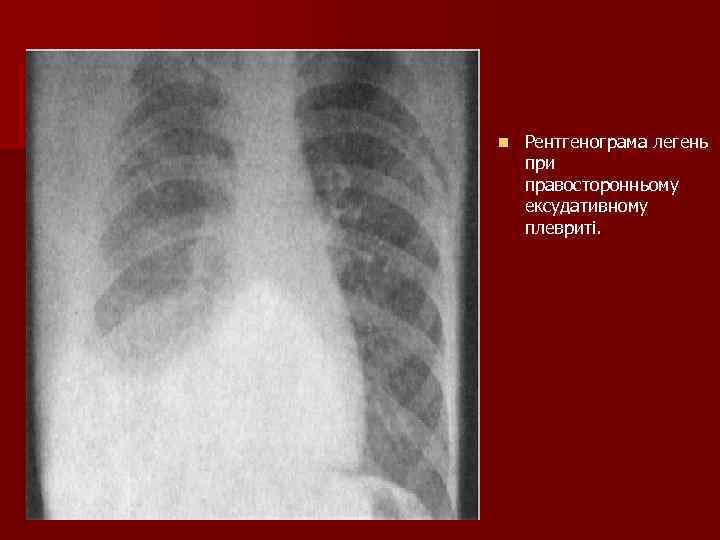

n Рентгенограма легень при правосторонньому ексудативному плевриті.

Рентгенологічно: n Дифузне накопичення рідини в плевральній порожнині 2 проекції – визначення осумкованої рідини Плевральна пункція n Проба Рівальта (білка більше 3%) n Бактеріологічне дослідження n Цитологічне дослідження (цитопатологія) n УЗД – показує шар рідини n Лабораторно: реакції на запальний процес - Збільшення ШОЕ - Ядерний зсув вліво - Підвищення вмісту фібрину, серомукоїду, сіалових кислот, фібрину.

Ексудативний плеврит. Патогенетичні чинники. - Рідина в плевральній порожнині стискає легеню => задишка. - Накопичення великої кількості рідини супроводжується розгладжуванням міжреберних проміжків, вип’ячуванням ураженої половини грудної клітки, відставання її при акті дихання. - Голосове тремтіння над рідиною не визначається або різко ослаблене.

Пальпація та перкусія при ексудативному плевриті n 1. Голосове тремтіння відсутнє в зоні ексудату. n Голосове тремтіння посилене над компресійним ателектазом (трикутник Гарлянда) - Порівняльна: в зоні ексудату – абсолютна тупість, над ексудатом, де трик. Гарлянда – притуплений тимпаніт. - Топографічна перкусія: верхня межа ексудату розміщується по лінії Соколова-Еліса Дамуазо.

Аускультативні зміни при ексудативному плевриті 1. Дихання над зоною ексудату – ослаблене везикулярне або зовсім відсутнє. 2. Над трикутником Гарлянда – ослаблене, бронхіальне дихання, крепітація. 3. Бронхофонія над зоною ексудату -над ексудатом відсутня. 4. Над компресійним ателектазом (Гарлянда) – посилене.